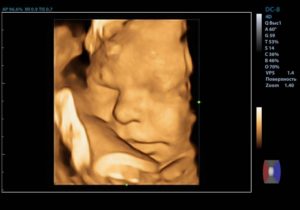

На 38 недели плановое УЗИ назначается редко. В таком возрасте уже прекрасно видно ребенка, можно разглядеть черты его лица. Врач, проводя обследование на этом сроке, оценивает состояние плаценты, расположение плода и пуповины, подсчитывает сердечные сокращения.

Фото плода

Предлагаем вам напоследок посмотреть фото плода на 38 неделе беременности.